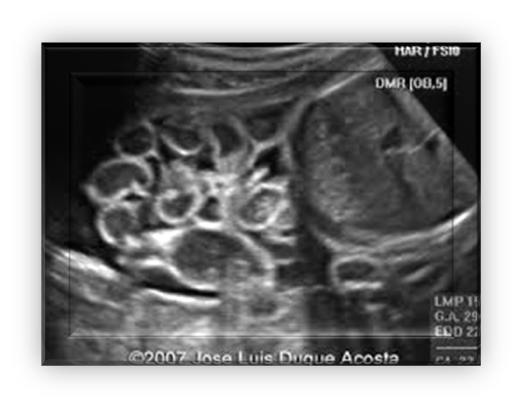

bowel obstruction

Bowel dilation